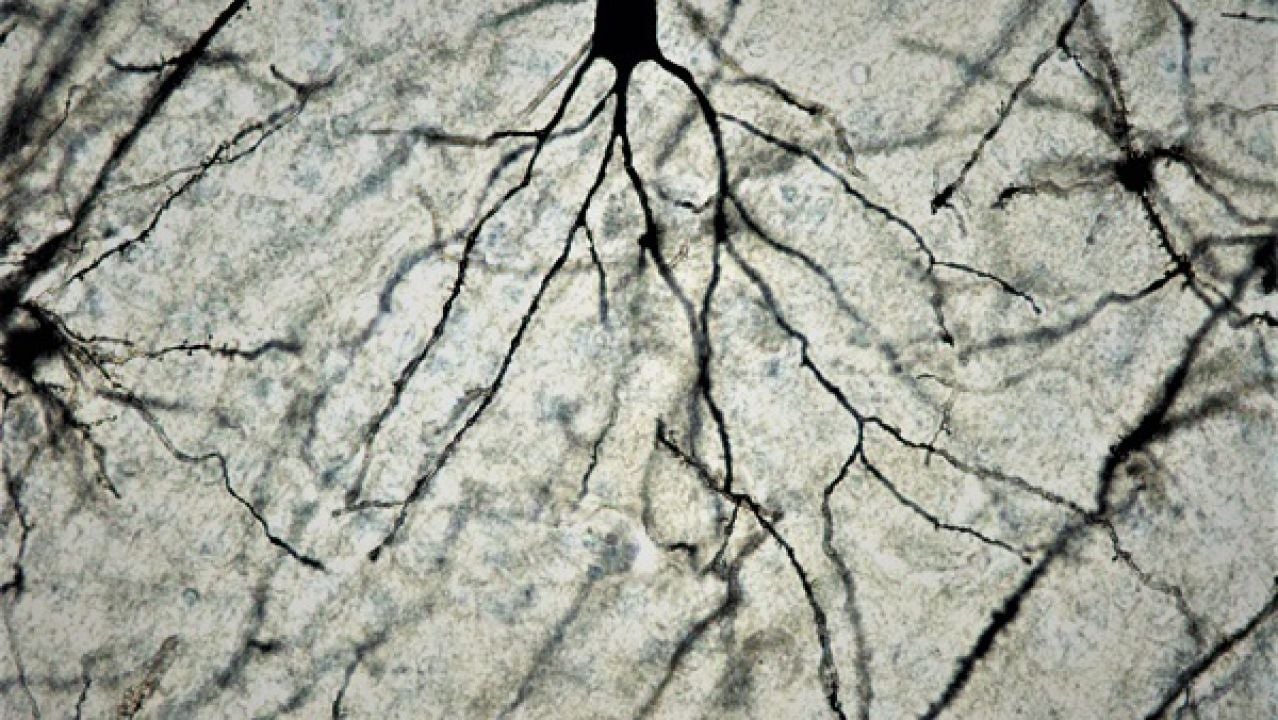

Neurona de cerebro de ratón a 100x tras tinción de Golgi-Cox. / Facultad de Medicina UCM. Sinc